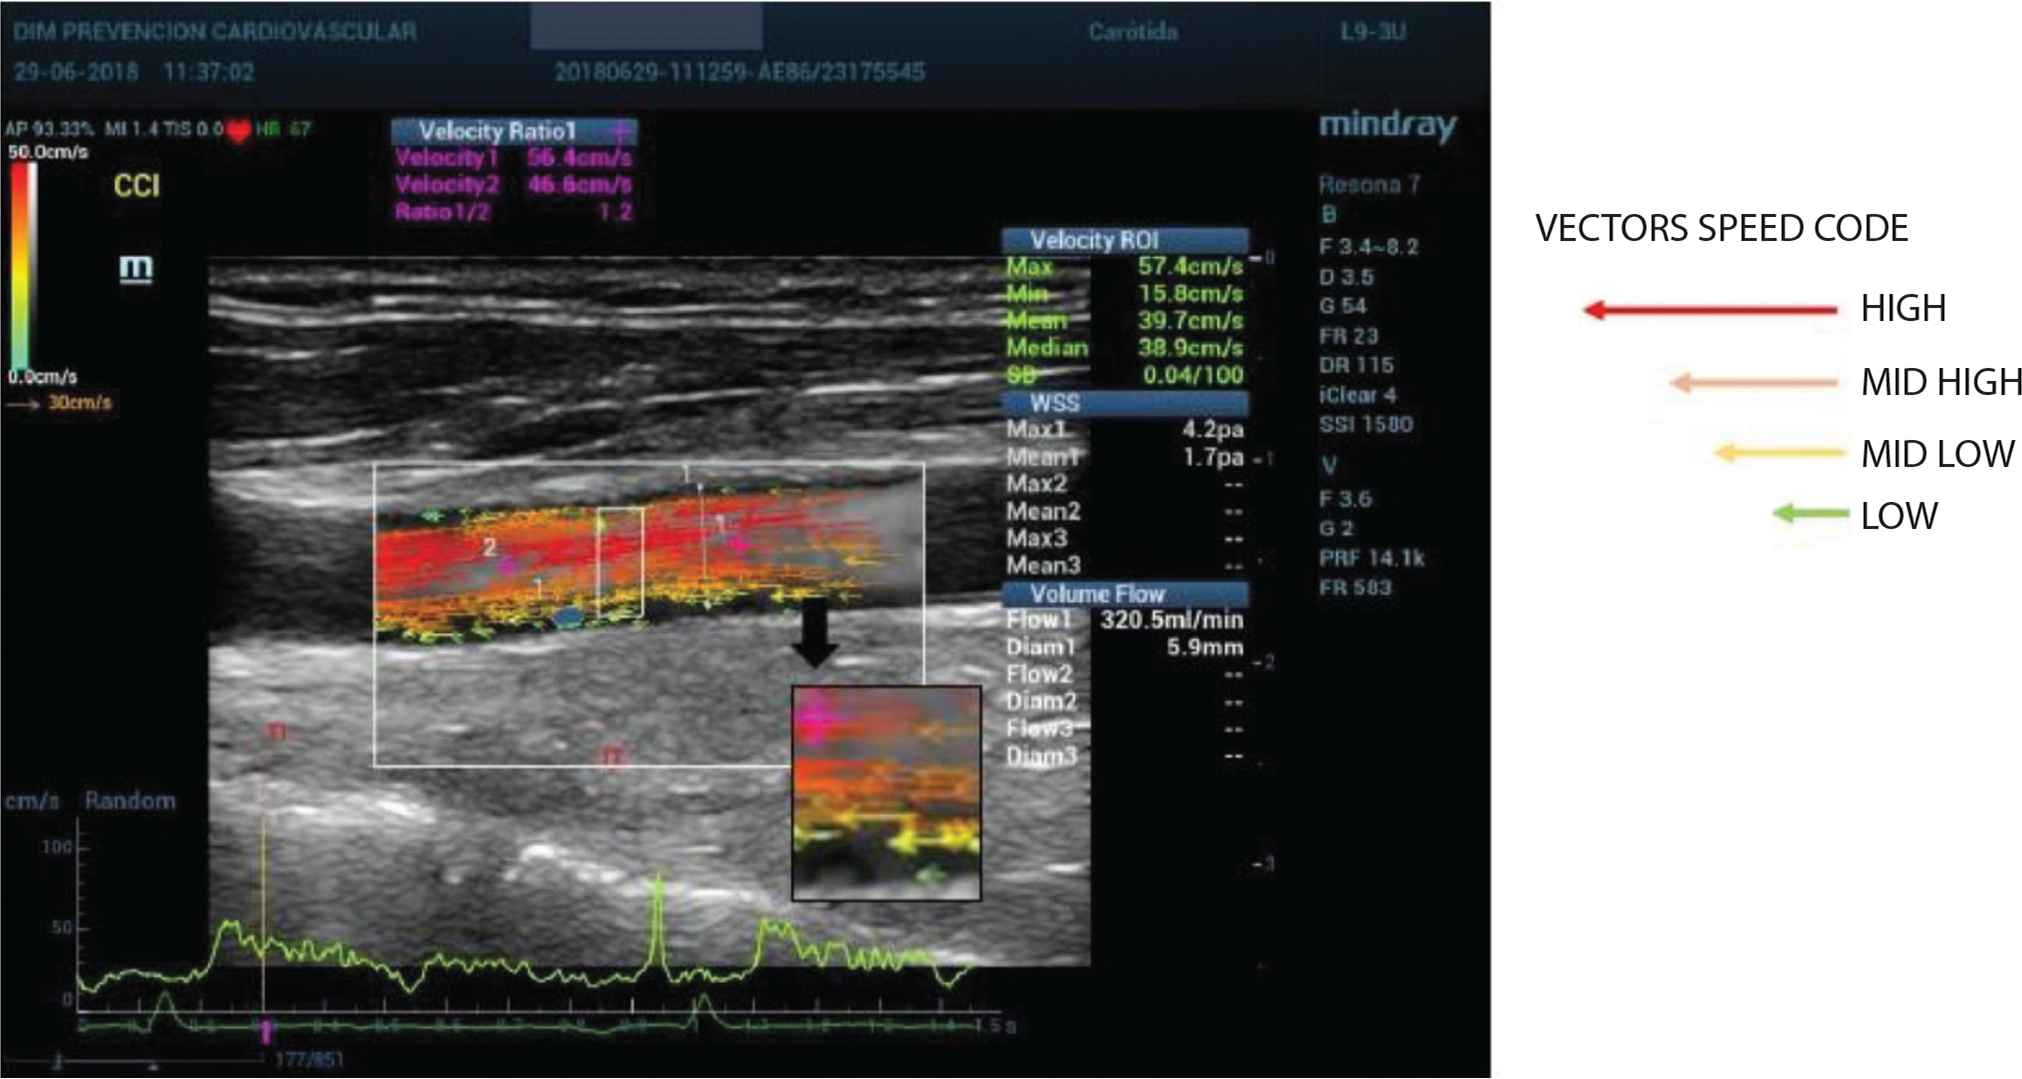

Methods: We evaluated 43 consecutive patients (18 healthy referent, 12 controlled HTN y 6 non controlled HTN) derived for NIVE (IMT, Plaques, PWV c-f and Endothelial Function) (“systemic parameters”) and using a new US machine Resona 7® with radiofrequency and multidimensional Doppler (VFlow) we obtained “regional parameters” of the common carotid artery like remodeling, arterial stiffness, wall shear stress and hemodynamic data like instantaneous speed and flow and speed gradient. The protocol was approved by LEC.